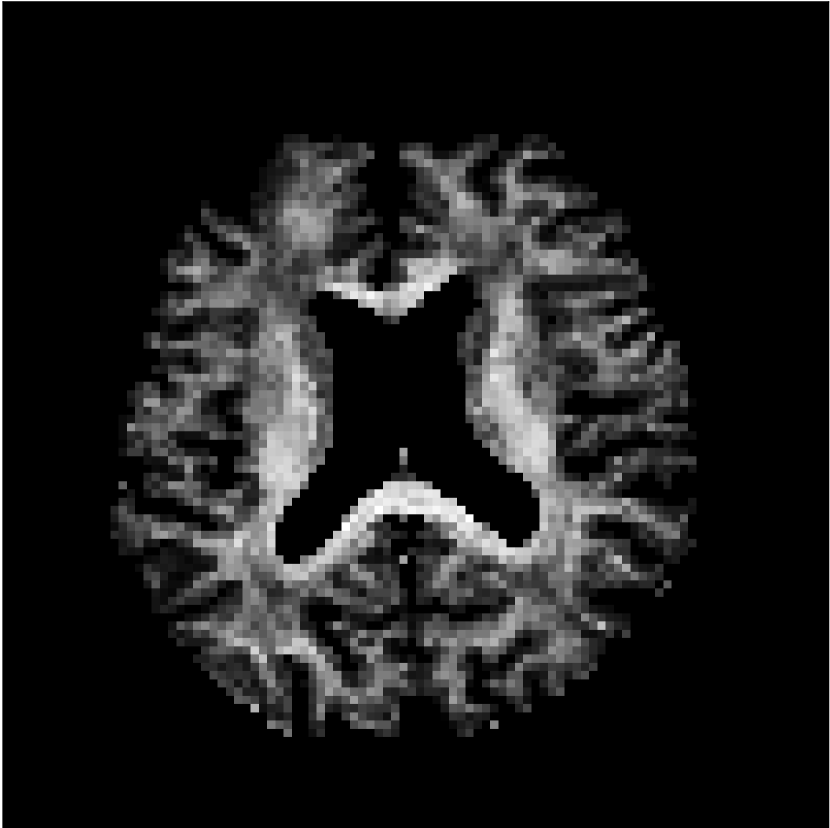

Figure 8 shows examples of non-diffusion-weighted images before and after processing. The raw images (Raw) served as the input for the magnitude deep learning (MCNN) and complex deep learning (CCNN) methods.

Raw 𝐱tsubscript𝐱𝑡\mathbf{x}_{t}

MCNN, fθ^(𝐱t)subscript𝑓^𝜃subscript𝐱𝑡f_{\hat{\theta}}\left(\mathbf{x}_{t}\right)

MCNN Resid., Ric(𝐱t)fθ^(𝐱t)Ricsubscript𝐱𝑡subscript𝑓^𝜃subscript𝐱𝑡\text{Ric}(\mathbf{x}_{t})-f_{\hat{\theta}}\left(\mathbf{x}_{t}\right)

CCNN, fθ^(𝐱t)subscript𝑓^𝜃subscript𝐱𝑡f_{\hat{\theta}}\left(\mathbf{x}_{t}\right)

CCNN Resid., Ric(𝐱t)fθ^(𝐱t)Ricsubscript𝐱𝑡subscript𝑓^𝜃subscript𝐱𝑡\text{Ric}(\mathbf{x}_{t})-f_{\hat{\theta}}\left(\mathbf{x}_{t}\right)

No PF

5/8 PF

Figure 8: Examples of non-diffusion-weighted images from in vivo data at b=0𝑏0b=0 s/mm2. Artifacts in the Raw image, 𝐱tsubscript𝐱𝑡\mathbf{x}_{t}, are corrected by the MCNN and CCNN models, fθ^(𝐱t)subscript𝑓^𝜃subscript𝐱𝑡f_{\hat{\theta}}(\mathbf{x}_{t}). Also shown are the residuals between the CNN corrections and the original Raw image with Rician bias correction Ric(𝐱t)Ricsubscript𝐱𝑡\text{Ric}(\mathbf{x}_{t}) [10]. The Gibbs artifacts removed by the methods are observed in the residuals. The MCNN method introduces some banding artifacts at the PF 5/8ths factor that are not present in the CCNN method.

Both methods remove artifacts, but the MCNN method allows residual rippling artifacts to pass through in the presence of partial Fourier. These rippling artifacts are not present in the CCNN method.